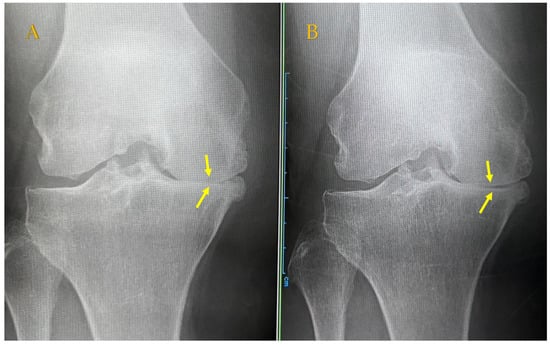

In addition, combined treatment may be expected to produce anti-inflammatory and cell proliferation effects, as seen on radiographs of the KL4 front-of-knee OA of a 64-year-old woman before APS therapy and 48 months after APS therapy. This patient continued ESWT approximately once or twice a month after the APS injection but showed a slight opening of the joint dehiscence compared with that before the APS injection (Figure 4). MRI of the same patient 48 months later showed the reduction in BML in T1 (upper photo), and the disappearance of bone cysts in T2 (lower photo) was confirmed (Figure 5). Since APS is a PRP product, it originally contains a large amount of TGFβ; however, the increased TGFβ level due to ESWT stimulation may have contributed to the anti-inflammatory effect and the regulation of cell proliferation and differentiation [,].

Figure 4.

Radiography findings in the Rosenberg view showing KL4 medial knee OA in a 64-year-old female patient. (A) Joint space before APS. (B) Joint space is expanded 48 months after APS + ESWT. APS, autologous protein solution; ESWT, extracorporeal shock wave therapy; KL, Kellgren–Lawrence classification; OA, osteoarthritis.